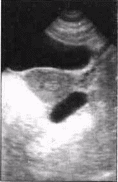

3. Абсцесс. В одной из параметральных областей лоцируется однокамерное жидкостное образование правильной округлой, реже овальной формы. Стенки плотные, толщина может достигать 8мм - результат воспалительной инфильтрации стенки трубы; контуры ровные, местами нечёткие и тяжистые за счет спаек. Размеры - не более 70 мм в диаметре. Структура содержимого неоднородная из-за множественных мелких включений (

фибрин, детрит), расположение которых меняется в зависимости от положения пациентки: при горизонтальном положении эти включения равномерно распределяются в полости образования, при вертикальном положении - смещаются в нижнюю часть полости. Аналогичный эффект - п

Рисунок 3. Левосторонний пиосальпингс.

одвижность внутриполостных включений, достигается компрессией полости датчиком (особенно ТВ). Этот симптом наблюдается при размерах патологического очага более 40 мм в диаметре. Форма включений либо вытянутая (длиной от 2 до 7 мм), либо они лоцируются как эхопозитивные точки. Плотность их низкая или средняя. Матка имеет обычный вид. У ряда больных на стороне поражения виден неизмененный яичник, оттеснённый в ту или иную сторону за счёт давления образования. Параметральные вены с двух сторон почти всегда расширены. Представленная УЗ-картина может быть расценена как ограниченный гидросальпингс с нагноением или, более точно, абсцесс маточной трубы (тубарный абсцесс).Тубарный абсцесс, по-сравнению с другими формами воспалительных изменений, встречается редко и, в рассмотренном здесь виде, отражает процесс частичной резорбции гноя на фоне продолжающейся экссудации с образованием так называемой "воспалительной кисты". Морфологический субстрат её - гнойный экссудат, ограниченный воспалительно изменёнными, местами истонченными стенками маточной трубы. При деструкции стенки возможен прорыв гнойника в брюшную полость с развитием пельвиоперитонита.